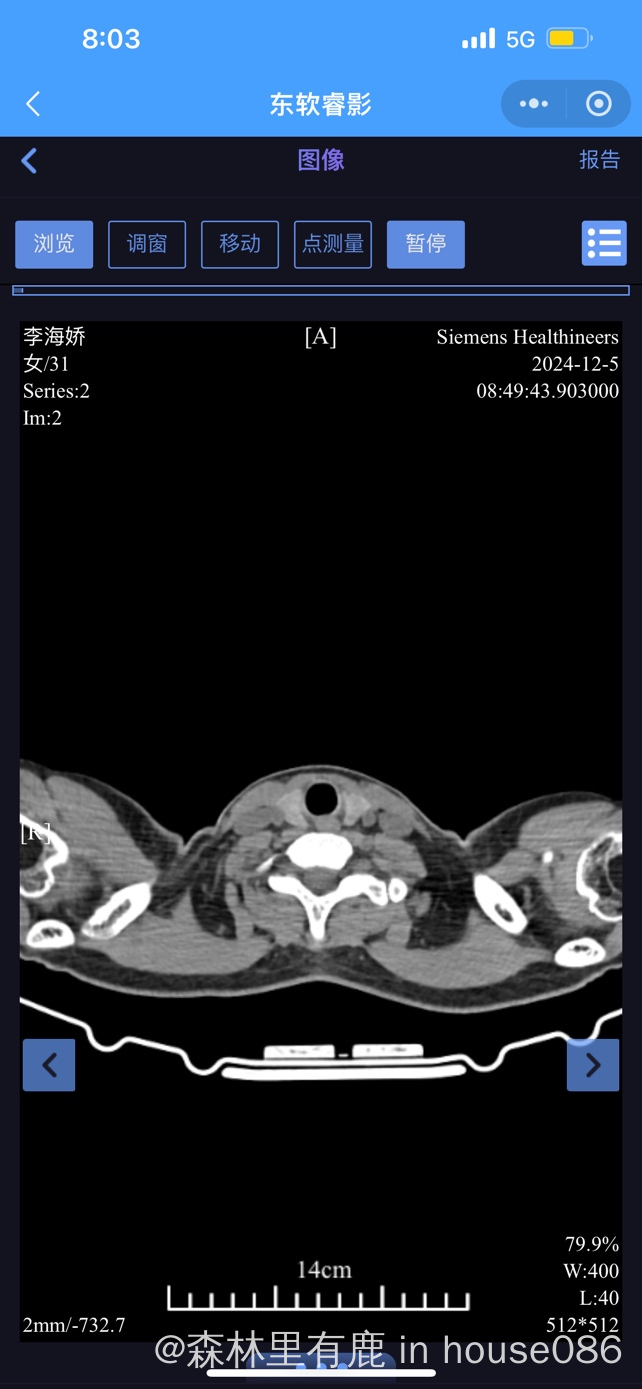

大家帮我看下胸部ct ,医生说右下肺叶很亚严重

现在也不知道是什么性质的肺炎,挂了几天抗生素,还每天会发烧几小时后才退烧

气管镜检查是不是新冠